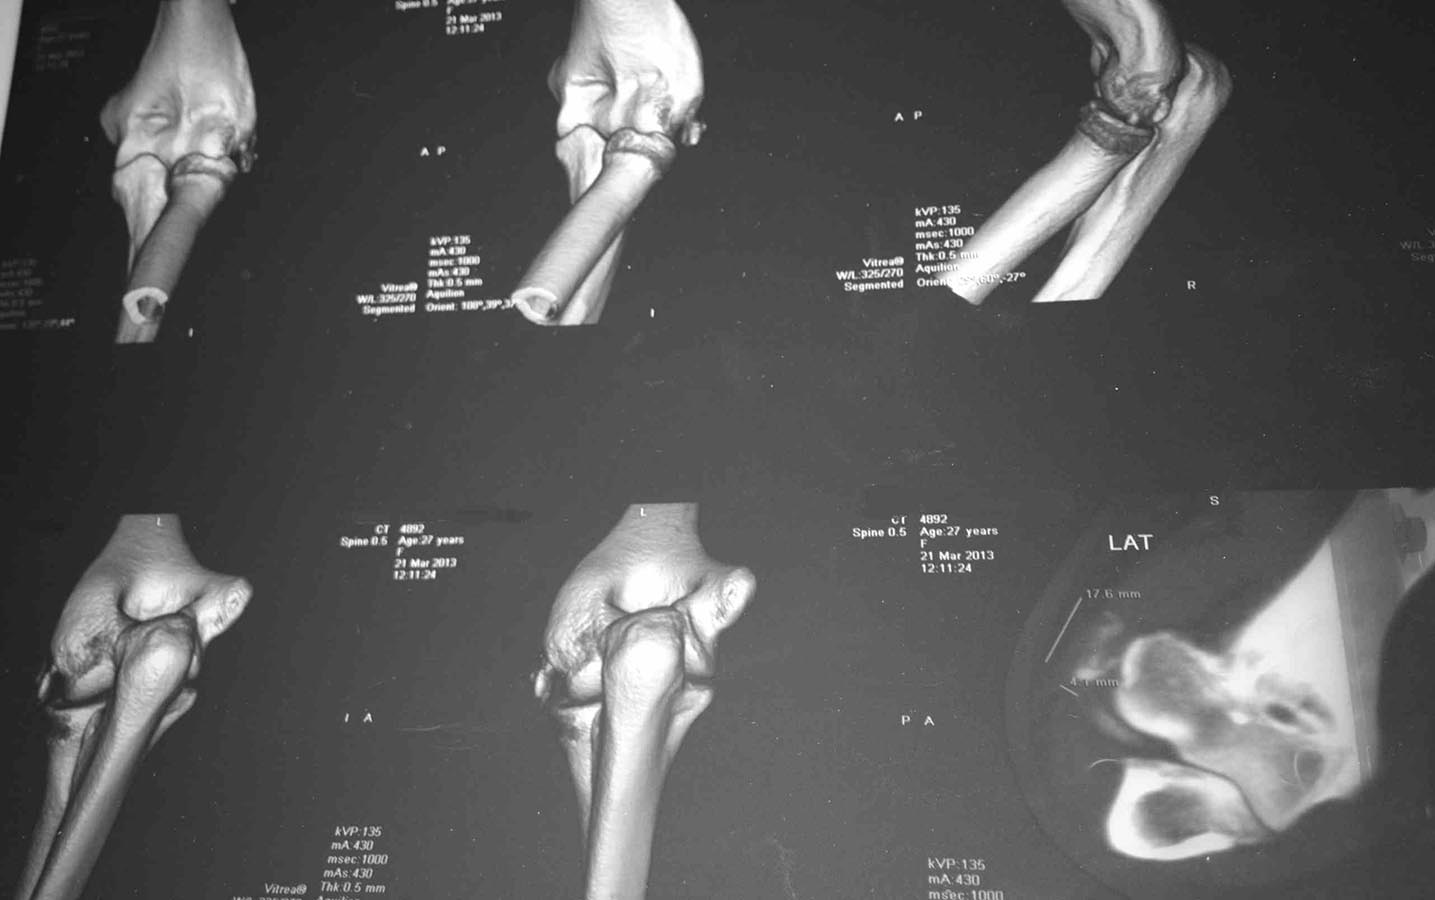

"Мне 27 лет. 15 марта заболела рука (левая; и я НЕ левша) в области локтевого сустава; не падала, тяжести не таскала, может недели за две до этого немного стукнулась локтем, но я полагаю, что если бы это было причиной, то боль появилась бы сразу, а не через 2 недели. Для общей картины еще-в 1995 году был перелом локтевой кости(трещина) и лучевой (закрытый со смещением) в области лучезапястного сустава). Симптомы: боль в локтевом суставе при сгибании\разгибании. Больно,но терпеть можно. 16 марта: рука ограниченно движется-процентов на 40 из всего во возможного, боль усилилась, Сделали рентген( в больнице "X")-поставили диагноз- латеральный эпикондилит.С 17 марта боль стала адской, рука отекла, шевелить невозможно даже пальцами, Все предплечье сковала сильнейшая непроходящая судорога(спазм). Рука онемевает, В пальцах чувствительность снижена. Боль вызывал даже воздух,попадающий на руку. Делала инъекции внутримышечно -мовалис(по 1 ампуле\3 дня), и дексалгин(по 3 ампулы в день\по настоящее время)-получается в день 4 инъекции. Мази прописанные я не использовала, т.к. к руке прикосаться невозможно. Боль остается и по сей момент, хотя уже могу шевелить пальцами, и дексалгин ставлю 2 раза в сутки. К постоянной судороге добавилось еще периодическое подергивание током (не знаю как описать правильно это, но так же, когда локтем стукаешься и током фигачит ). Ах да..сегодня гипс наложили ("на всякий случай"(с) )Температура нормальная (за исключением нескольких дней, когда без обезболивающего еще была-навыла себе температуру до 37.5 ), анализ крови не делали. Ревматолог сказала, что это не по ее профилю. Поэтому бегаю от хирурга к травматологу и обратно."Для какой болячки может быть характерна такая клиника и картинка? Для латерального эпикондилита такая "отшнуровка" нехарактерна. В каком направлении размышлять, какое дообследование назначить?

Фрагмент, который определяется на снимке, на мой взгляд, это оссификация коллатеральной связки. А вот как связать оссификацию с такой неврологической симптоматикой - не представляю.

На снимках похоже на рассекающий остеохондрит медиального надмыщелка плечевой кости

Проблема в том, что проблема латерально, а с этой стороны таких фрагментов не бывает

Нет ли перелома головки ЛУЧЕВОЙ кости с невропатией лучевого нерва?

Может быть отрыв наружного надмыщелка плеча,постепенное (в течение двух недель) стягивание костных фрагментов прикрепляющимися мышцами в дистальном направлении до суставной щели + процесс рубцевания, привели к травматической невропатии глубокой ветви лучевого нерва,усилению болей? Тогда ревизия головчато-лучевого сустава,невролиз глубокой ветви лучевого нерва,подшивание проксимального конца мышцы (с костным фрагментом или без) к наружному надмыщелку.